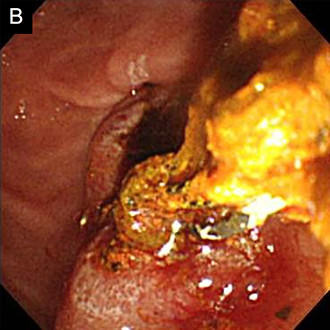

図4 総胆管結石の内視鏡治療

総胆管結石の内視鏡的な完全除去が可能でした。

A. 内視鏡的胆管造影で複数の総胆管結石を確認しました (↓)。

B. 乳頭切開を行い、全結石を除去しました。

• 内視鏡治療画像:内視鏡的胆管造影で複数の総胆管結石を確認

• 内視鏡治療画像:乳頭切開を行い、全結石を除去